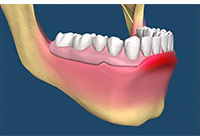

上顎犬齒是牙齒萌發順序最晚的牙齒,加上它萌發的路徑較其他牙齒長,這也造成上顎犬齒是上顎最常見的阻生牙。女性的好發率也高於男性。上顎機率高於下顎。診斷出上顎犬齒阻生需要靠臨床觀察與影像學判斷。在影像學方面,根尖片雖然是一個二維的影像,但是可以顯示牙齒與鄰牙間的相對關係。而確切的位置評估則需要藉由電腦斷層來定位。如果較晚發現犬齒已異位萌發,則可以藉助翻辫瓣手術將矯正器黏在犬齒,並用矯正力量拉下犬齒。 (圖05-08)

圖5